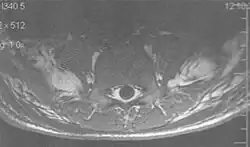

A motion artifact is one of the most common artifacts in MR imaging.[2] Motion can cause either ghost images or diffuse image noise in the phase-encoding direction. The reason for mainly affecting data sampling in the phase-encoding direction is the significant difference in the time of acquisition in the frequency- and phase-encoding directions.[1] Frequency-encoding sampling in all the rows of the matrix (128, 256 or 512) takes place during a single echo (milliseconds). Phase-encoded sampling takes several seconds, or even minutes, owing to the collection of all the k-space lines to enable Fourier analysis. Major physiological movements are of millisecond to seconds duration and thus too slow to affect frequency-encoded sampling, but they have a pronounced effect in the phase-encoding direction. Periodic movements such as cardiac movement and blood vessel or CSF pulsation cause ghost images, while non-periodic movement causes diffuse image noise (Fig. 1). Ghost image intensity increases with amplitude of movement and the signal intensity from the moving tissue. Several methods can be used to reduce motion artifacts, including patient immobilisation, cardiac and respiratory gating, signal suppression of the tissue causing the artifact, choosing the shorter dimension of the matrix as the phase-encoding direction, view-ordering or phase-reordering methods and swapping phase and frequency-encoding directions to move the artifact out of the field of interest.[1]